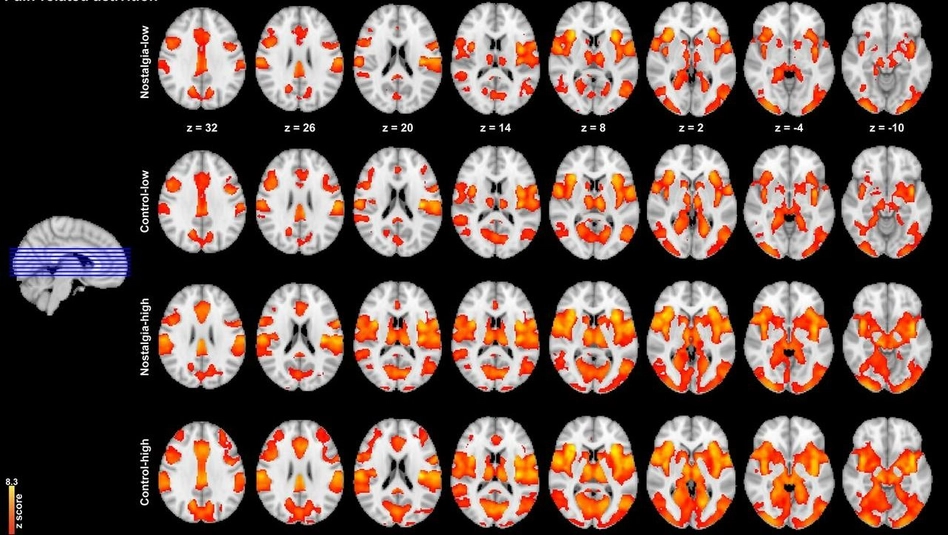

Mientras las personas miraban esas fotos, se tomaban imágenes de resonancia magnética de sus cerebros. La resonancia magnética es un método no invasivo que no involucra cirugía ni agujas, de mucha utilidad en la clínica y en la investigación. Permite ver qué zonas del cerebro están más activas en un momento dado, por ejemplo, al momento de mirar una foto.

Los primeros resultados de estos experimentos mostraron que si el estímulo de dolor se daba después de una foto que evocaba nostalgia, la percepción del dolor era menor. Es decir, la nostalgia parece tener un efecto analgésico. Pero además, las imágenes de resonancia magnética mostraban que las zonas del cerebro asociadas al dolor se activaban menos luego de mirar las fotos nostálgicas. Esto confirmaría lo que las personas completaban en las encuestas.

En resumen, el trabajo sugiere que la nostalgia evocada por fotos “desactiva” ciertas regiones del cerebro, provocando una menor percepción del dolor. La región del cerebro que parece estar participando de esta conexión, entre nostalgia y dolor, es una región anatómica que se llama tálamo.